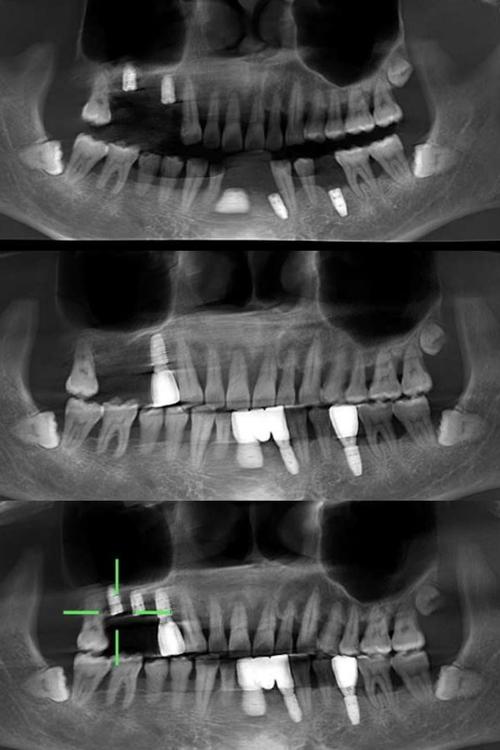

当X光检查提示骨量不足、解剖结构复杂(如下颌神经管位置靠近牙槽嵴、上颌窦低垂)或需进行复杂种植(如全口种植、穿颧种植)时,CT检查(尤其是口腔专用锥形束CT,CBCT)是必不可少的一步。

- 三维可视化:可任意角度旋转、切割图像,直观显示牙槽骨的立体形态,精确测量骨高度、宽度、厚度(误差可控制在0.1mm以内);

- 高分辨率:能清晰分辨下颌神经管、上颌窦底、颏孔等重要解剖结构的位置、边界及与牙槽嵴的距离;

- 规避神经血管损伤:对于下颌后牙区种植,CBCT可精确标记下颌神经管的走行,确保种植体尖端距离神经管至少1-2mm;

- 数字化种植导板设计:基于CBCT数据,结合口内扫描模型,可制作3D打印种植导板,引导种植体精准植入预定位置,误差小于0.5mm,尤其适合全口无牙颌种植或即刻种植病例。